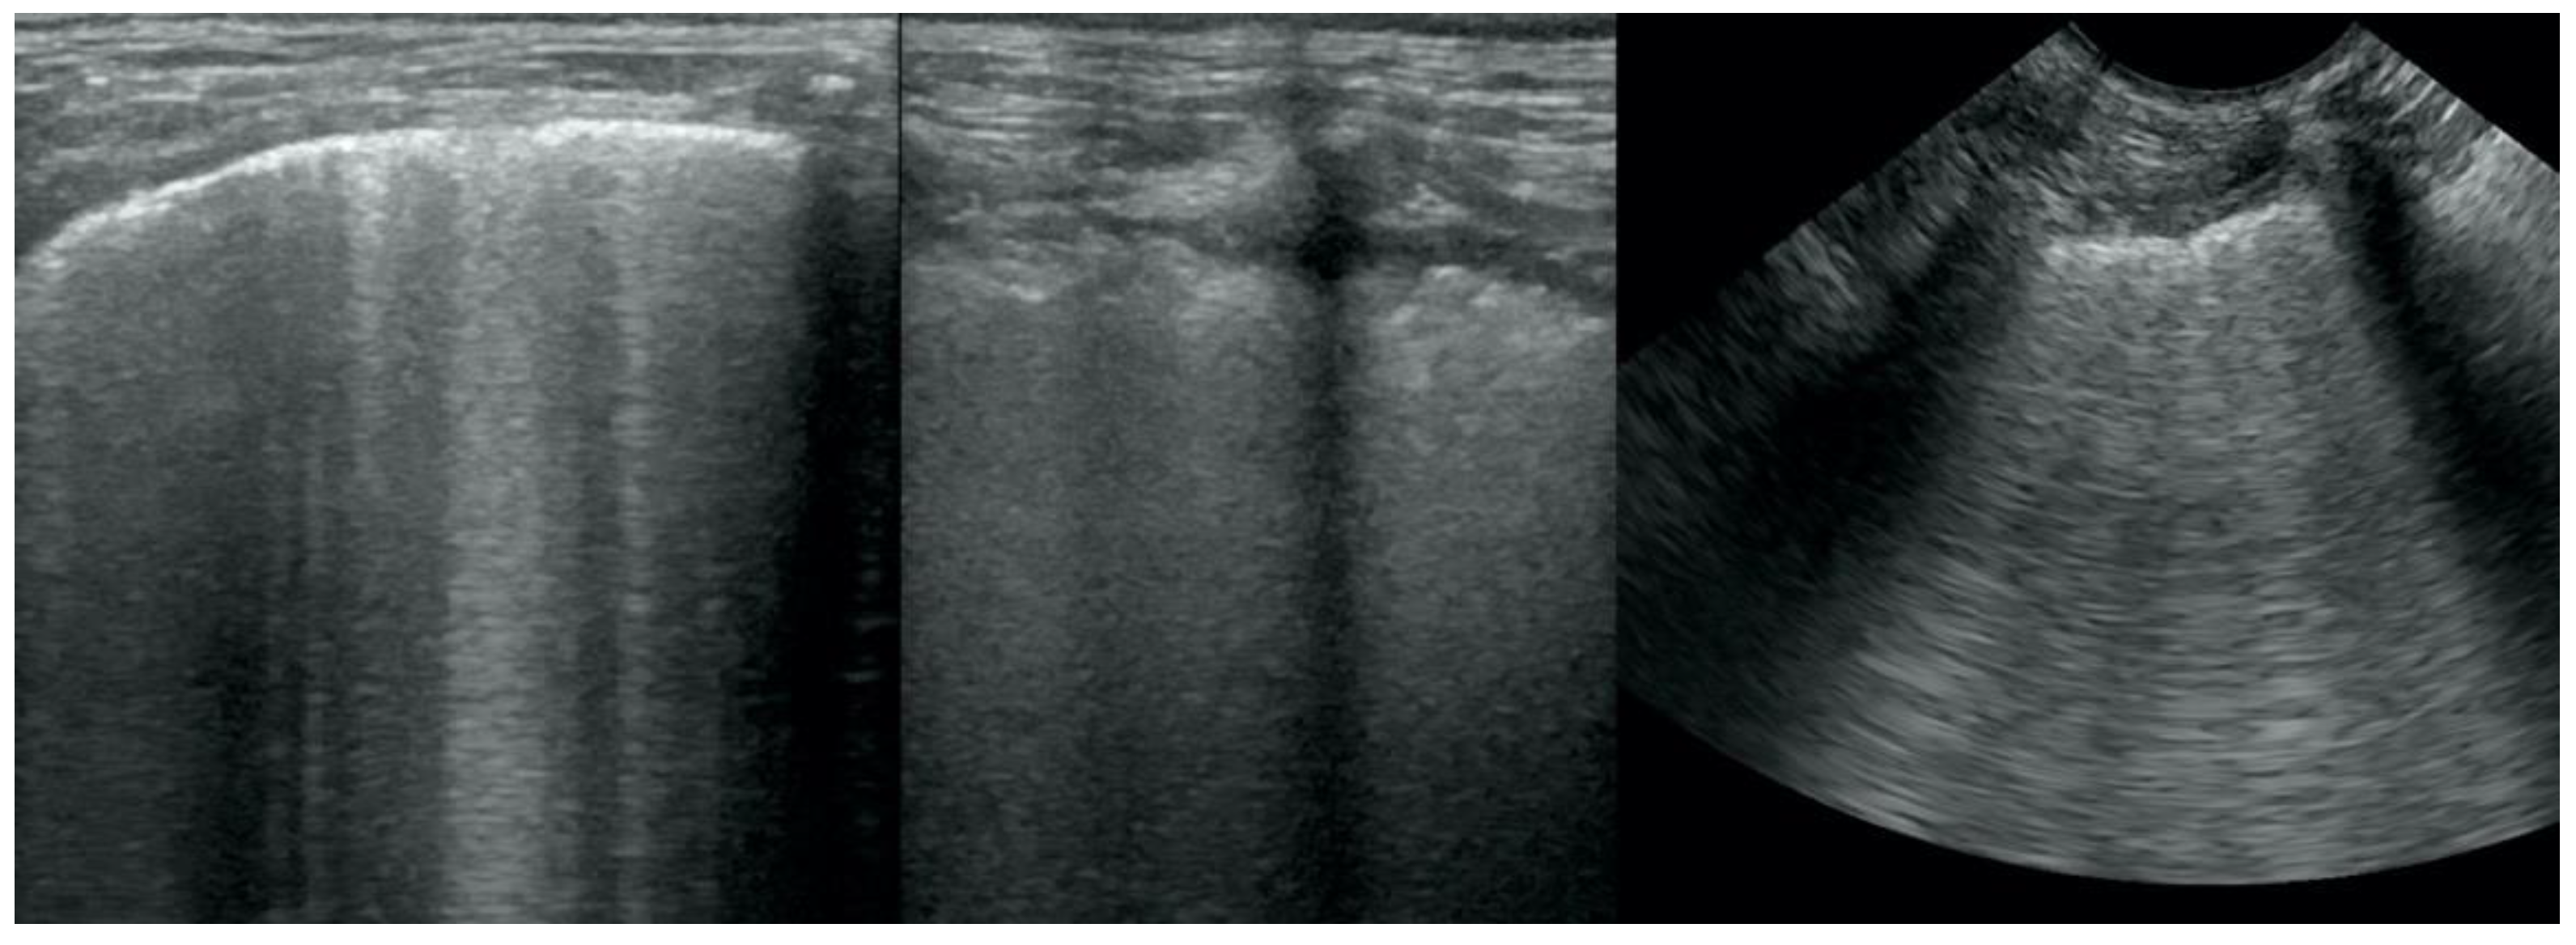

Stylized Photographic Depiction Of The Vetblue Technique For Lus A Download Scientific Diagram

Lung Ultrasound Flooding In Fulminant Pulmonary Oedema In Cats And A Comparison With Pneumonia Vet Practice Support

Thoracic Ultrasound A Method For The Work Up In Dogs And Cats With Acute Dyspnea

Presentation1 Ultrasound Examination Of The Chest